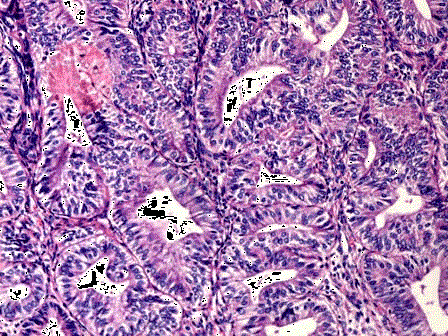

问题 女性,46岁,阴道不规则出血1年,诊刮子宫内膜,显微镜下见腺体增生密集,与间质比>3:1,腺体呈乳头状,可见背靠背现象,伴嗜酸性粒细胞浸润,腺上皮异型性并见核仁(如图),应诊断为 ( )

选项 A.子宫内膜单纯性增生 B.子宫内膜复杂性增生 C.子宫内膜单纯性增生伴非典型增生 D.子宫内膜复杂性增生伴非典型增生 E.子宫内膜腺癌

答案 C